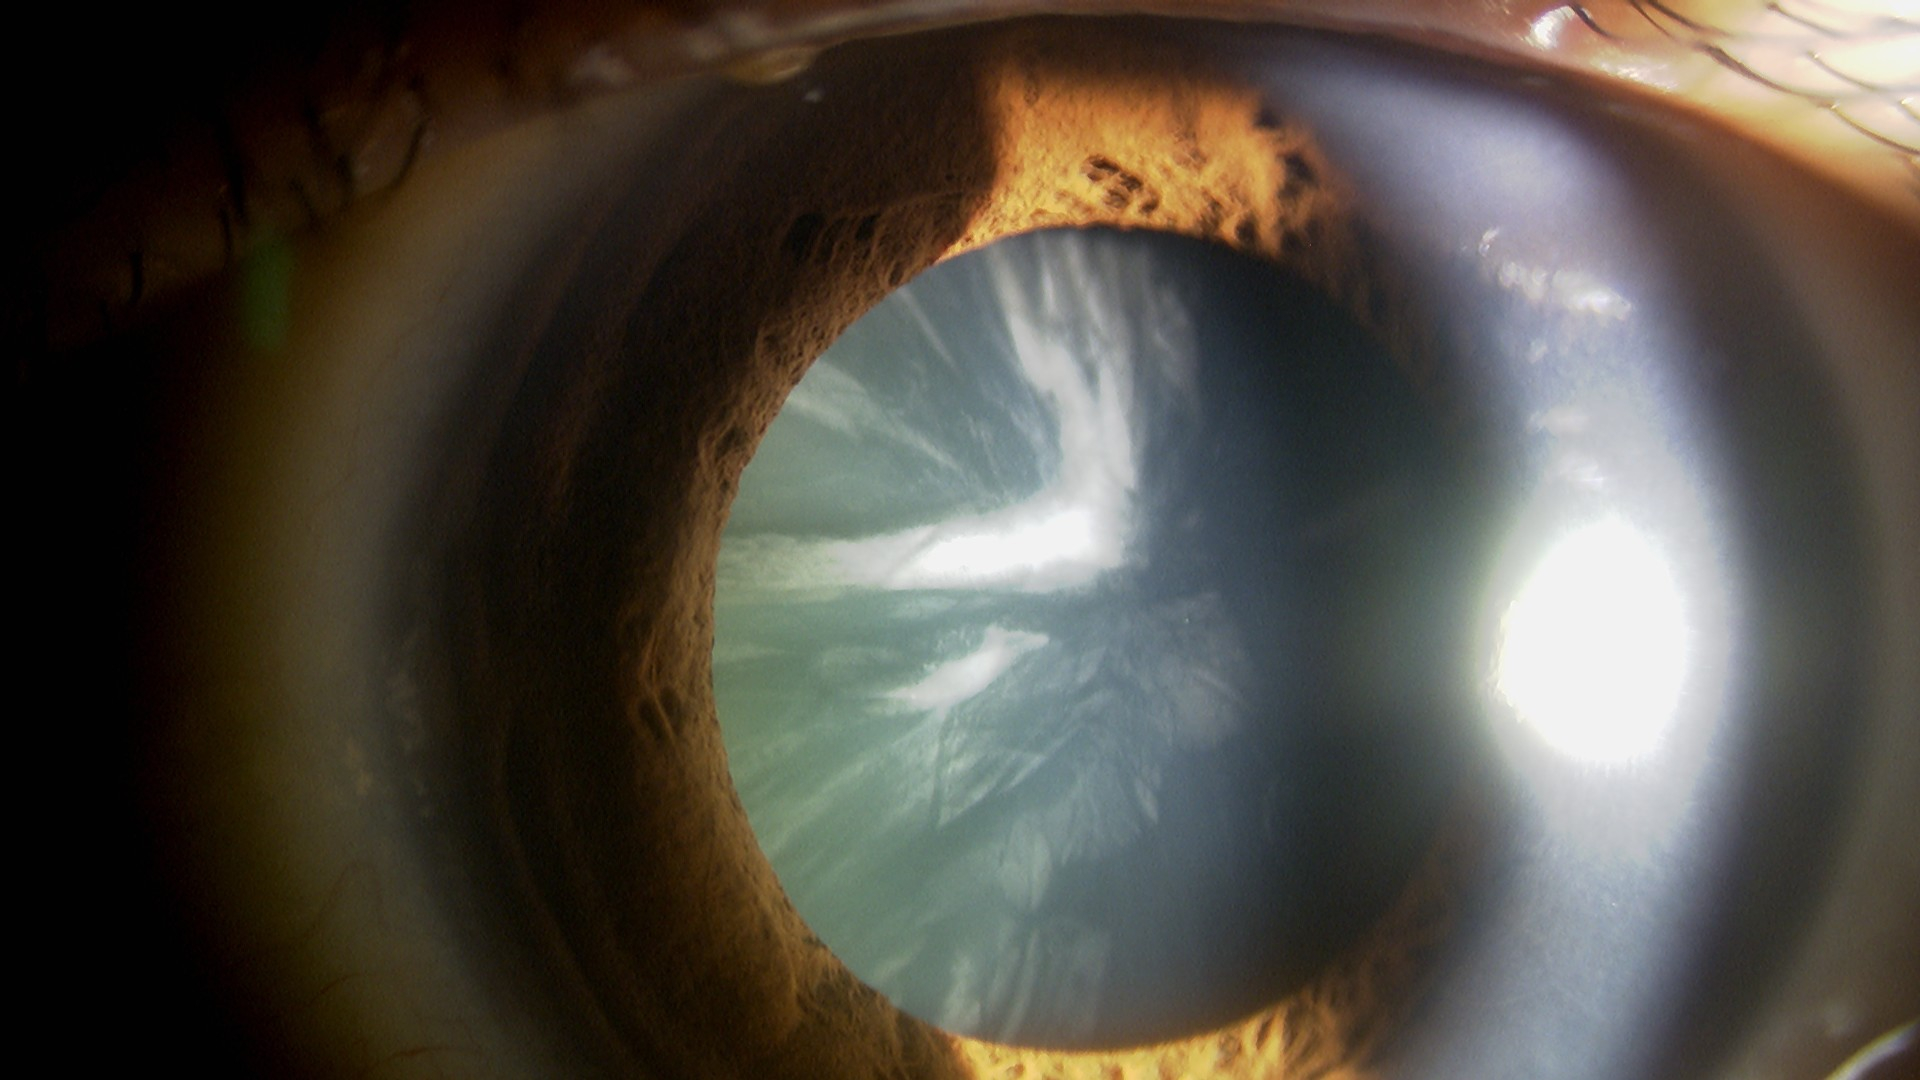

運転とパソコンを裸眼でしたい(もともと近視⇒多焦点眼内レンズ)

使用レンズ

右目:PanOptix

左目:PanOptix

水晶体再建術

遠見:右 0.06 (矯正0.6) 左 0.1 (矯正0.9)

近見:右 0.6 左 0.9

遠見:右 1.2 左 1.5

近見:右 1.0 左 1.0